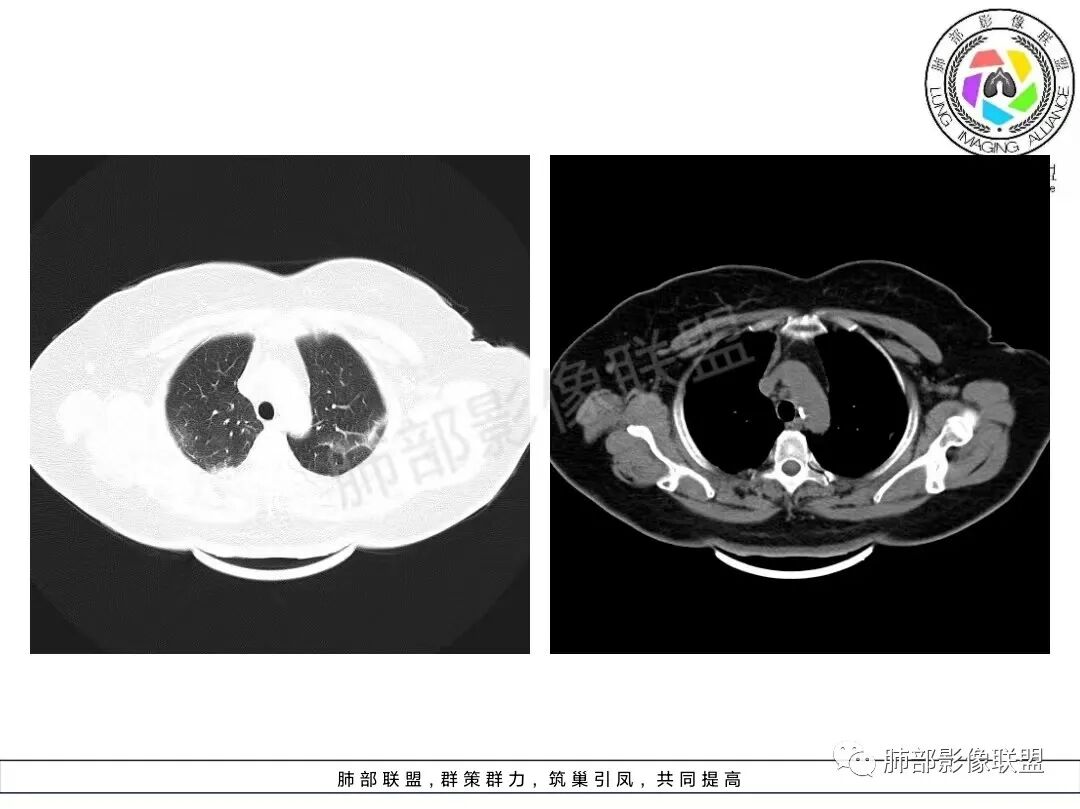

老年女性,咳嗽、咳黄白痰,无发热,化验炎性指标高,右肺胸膜下实变,其内支气管充气、扩张,周围索条,左肺胸膜下多发结节及斑片实变,胸膜下线影,右侧少量胸水,考虑机化性肺炎,鉴别隐球菌、粘液腺癌

双肺胸膜下多发实变,边界不清,较大病变长轴与胸膜平行,近端可见充气支气管征,部分病灶内坏死边界清,胸膜下有多发相类似病灶,综合考虑首选隐球菌,其次0P尚不除外

老年女性,咳嗽、咳黄白痰,无发热,右肺胸膜下实变,其内支气管充气、扩张,周围索条,左肺胸膜下多发结节及斑片实变,胸膜下线影,右侧少量胸水,考虑机化性肺炎。

2、影像特点:双肺胸膜下为主、多发斑片影、结节样实变影及磨玻璃样密度影,大部分病灶边缘平直、边界清,磨玻璃密度病灶内可见细网格影,部分病灶内可见支气管扩张表现,部分支气管直达远端,部分中断于病灶中部。部分病灶有侧向融合趋势。